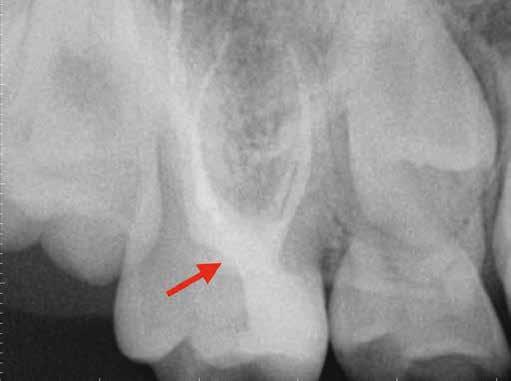

1. a–f ábrák: A cingulumon keresztül gömbfúróval kialakított hozzáférés a trepanációs kavitás labiális irányba történő túlzott mértékű kiterjesztését eredményezheti, és ez lényegesen növelheti a perforáció esélyét (a). A guttapercha átsejlik a lágyrészek alatt (b). Klinikailag igazolt perforáció (c). A preoperatív sagittális irányú CBCT-szeleten jól látható a labiális perforáció (d). Labiális irányú perforáció (fekete nyíl; e). A tényleges gyökércsatorna (piros nyíl; f).

2. a-b ábrák: A cingulumon keresztül gömbfúróval végzett trepanálás túlzott pericervikális dentin áldozattal, fordított tölcsér effektussal és perforációk kialakulásával járhat (fehér nyíl).

A frontfogakban történő hozzáférési nyílás kialakítása

A frontfogakban a hozzáférési nyílás kialakítását hagyományosan a fogak linguális vagy palatinális felszínén, a cingulumon keresztül egy gömbfúró segítségével kezdjük. A linguálisan elhelyezkedő kiemelkedés teljes eltávolítása, továbbá a pulpaszarvak teljes feltárása egy háromszög alakú hozzáférési nyílást eredményez. 7 Ezt a módszert a fogak esztétikai megjelenésének megőrzése érdekében fejlesztették ki. Ez azonban időnként a saját foganyag indokolatlan eltávolításával, a trepanációs kavitás labiális irányba történő túlzott kiterjesztésével, perforációval, valamint a fog kritikus helyen, a pericervikális dentin (PCD) területén történő meggyengítésével jár (1. a–f és 2. a-b ábrák). 19 Felmerült, hogy a pericervikális dentin rendkívül fontos szerepet játszik a rágóerő gyökerek irányába történő továbbításában, és elképzelhető, hogy a gyökérkezelt fogak hosszú távú megtartása szempontjából a legfontosabb tényező az ép pericervikális dentin megőrzése lehet. 20 A cingulumon keresztül történő hozzáférési nyílás

kialakítása során fennáll a fog labiális irányú perforációjának veszélye, mivel ilyenkor a foganyag elvételét labiális irányú fúrótartással kezdjük. Nemrégiben újragondolták a